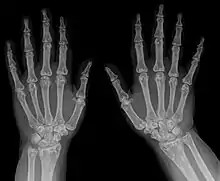

Diagnostic methodX-ray, ultrasound[3]

Osteopoikilosis

The diagnosis of this condition can be ascertained via several techniques one such method is genetic testing, as well as:[2][3]